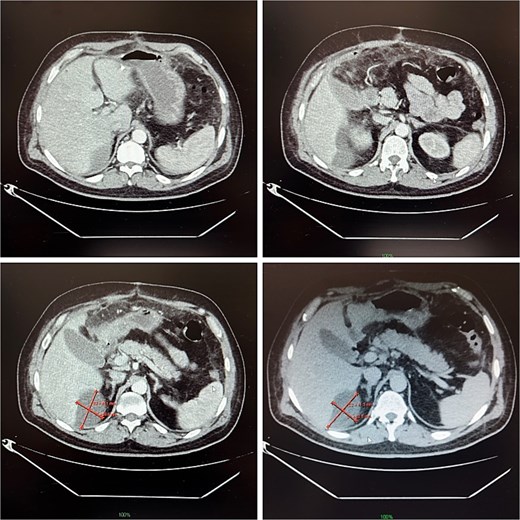

On postoperative day 14, the patient remained febrile. Computed tomography revealed a secondary abscess in segment VII (Fig. 2), which was successfully managed by percutaneous drainage under ultrasound guidance (Fig. 3). The regimen was subsequently switched to intravenous linezolid 600 mg twice daily, combined with antifungal therapy. The drains were gradually removed by postoperative day 30, while intravenous therapy continued until day 35. The patient was discharged on day 37.

(A and B) Abdominal ultrasound depicting a 9 × 5 cm abscess in segment VII. (C and D) Percutaneous drainage performed with placement of a 10 Fr catheter under ultrasound guidance.